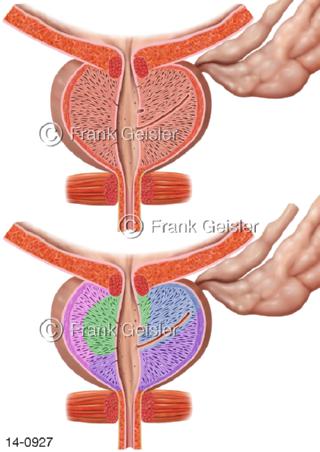

Bildergalerie Urogenitalsystem

Bilder zum Urogenitalsystem mit Urogenitalorgane, Urogenitaltrakt, zum Harn- und Geschlechtsapparat, Harnorgane und Geschlechtsorgane, Organe der Harnwege und der Fortpflanzung, Harnorgane und Geschlechtsorgane im männlichen und weiblichen Urogenitalsystem